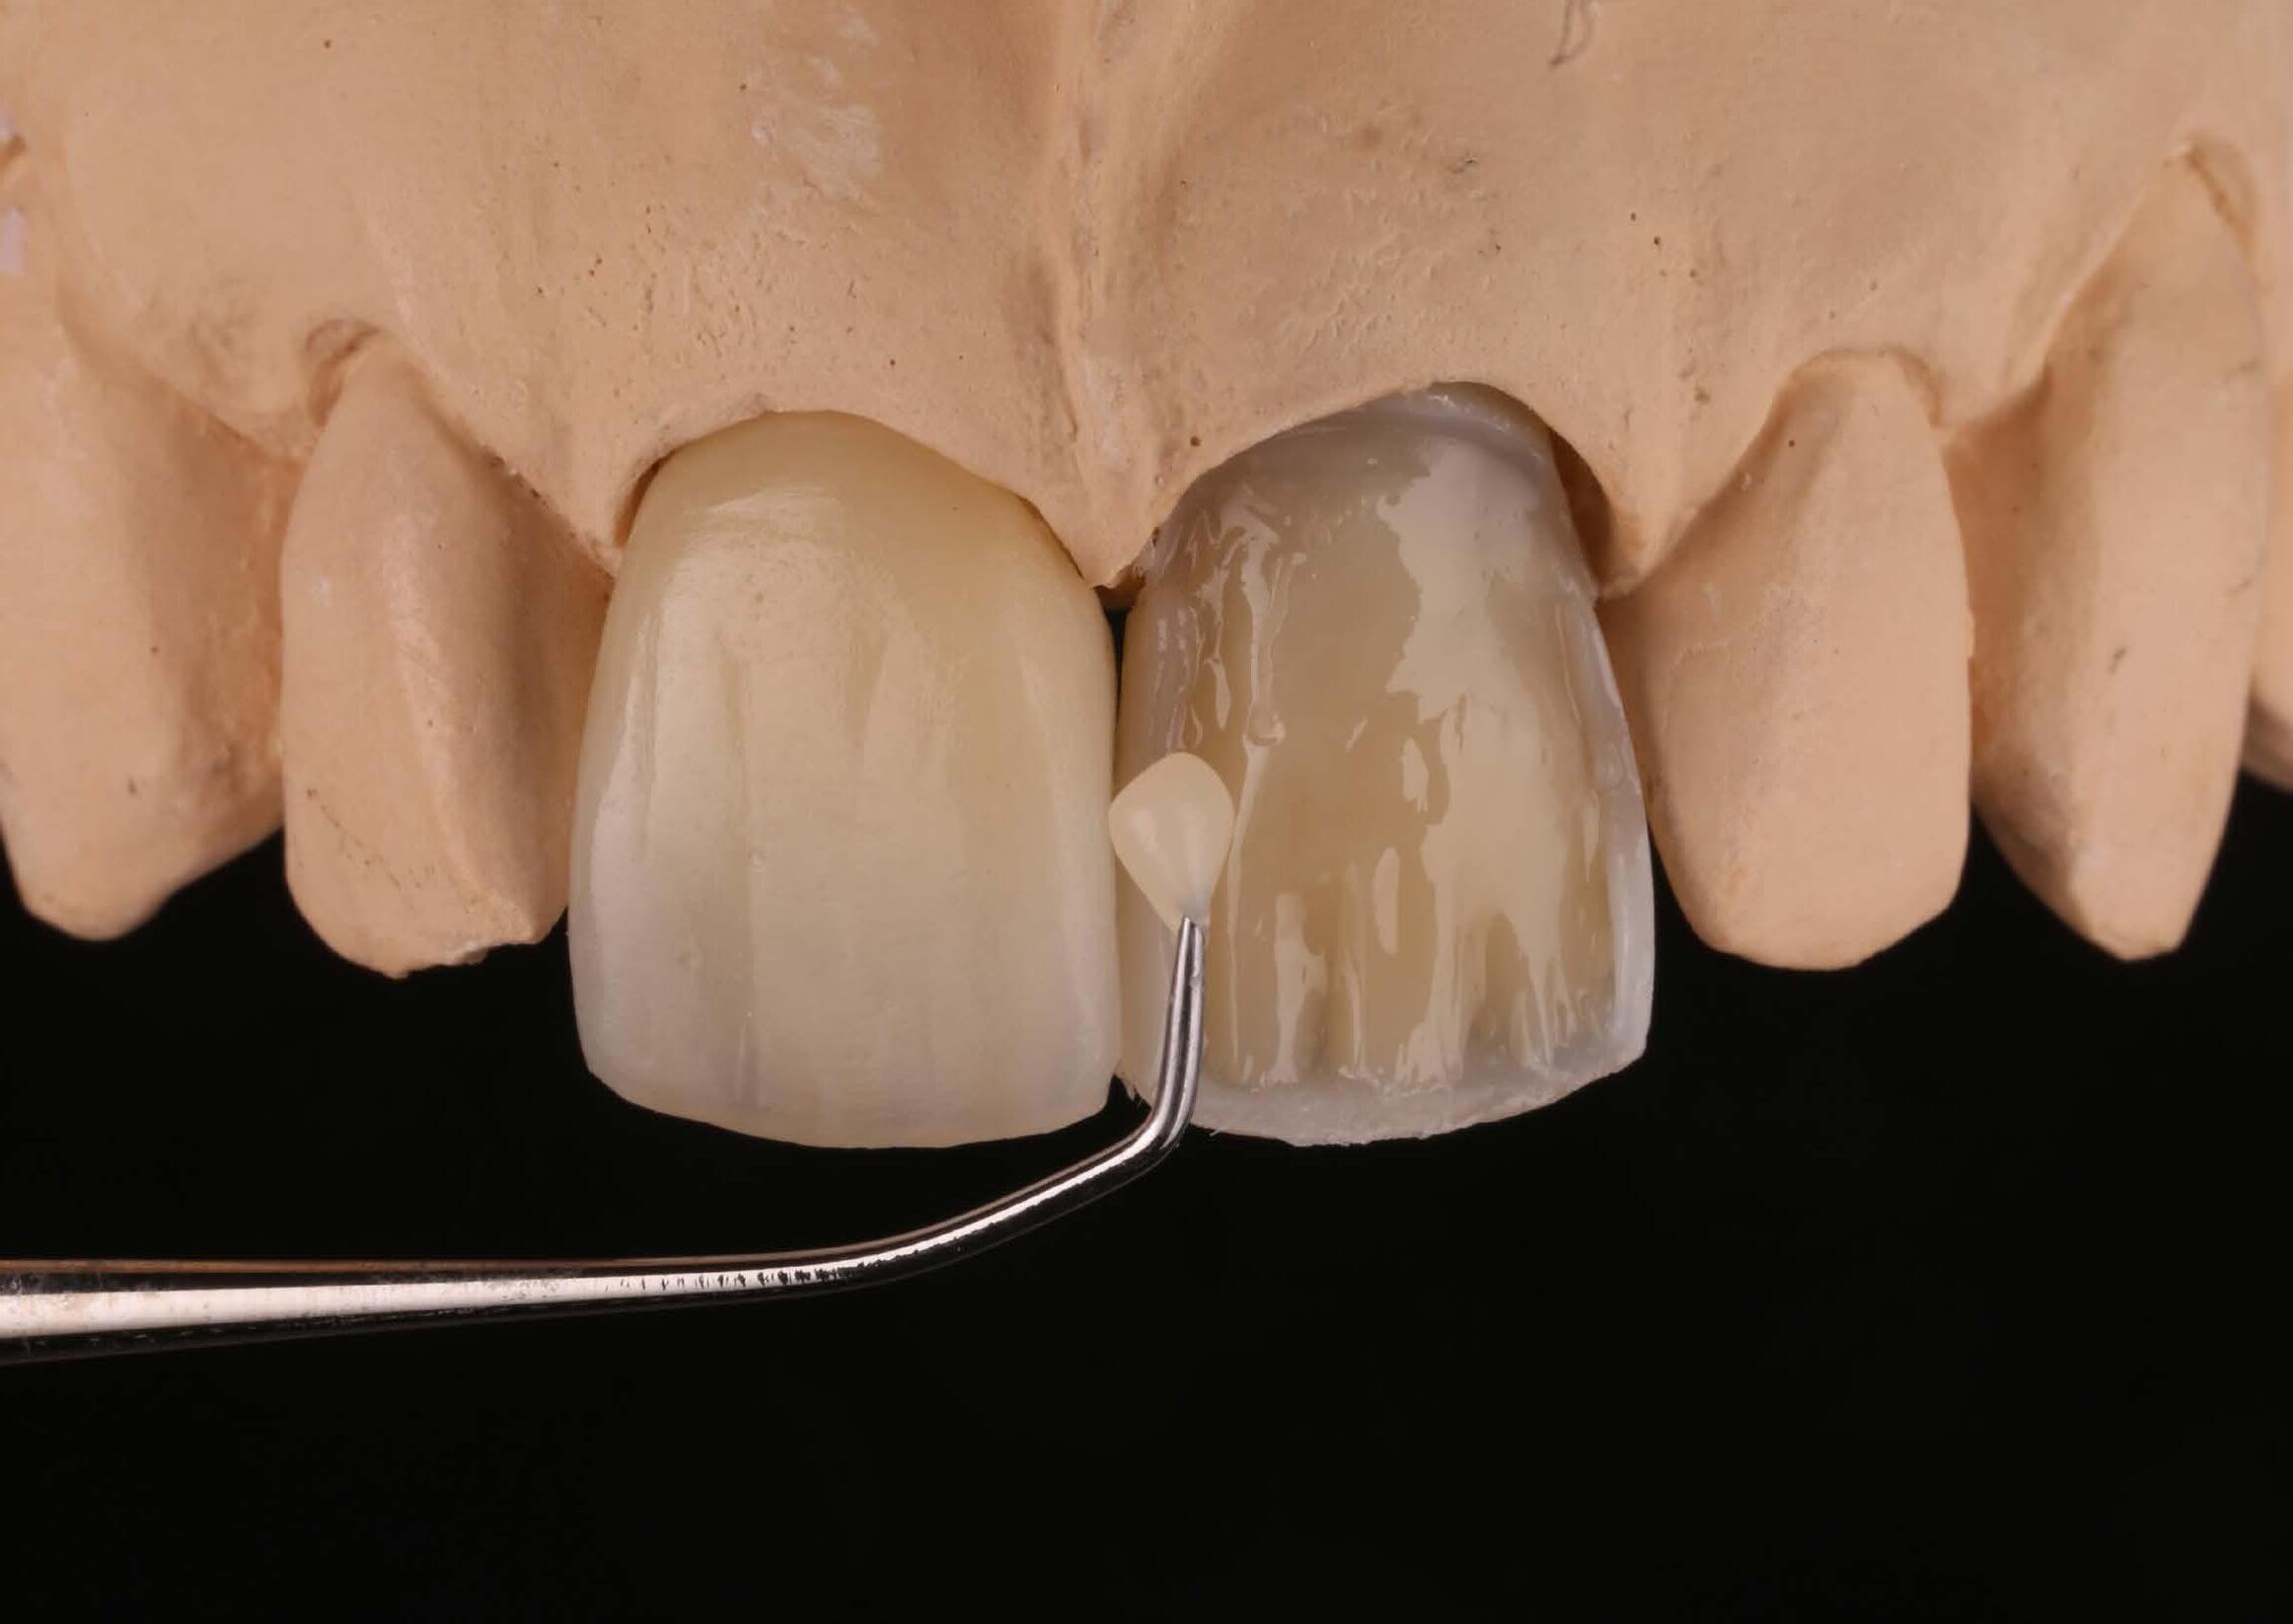

13 CPD Fri/Sat 8-9 NOV 8.30am - 5.00pm UWA DENTAL SCHOOL $2187 members

COURSE OUTLINE

There will be a substantial hands-on component to the course.

• Recognition of appropriate cases

• Case work-up

• Rationale for the design of relevant restorations

• Material options

• Occlusal registrations and articulation

• Bonding and cementation protocols

PRACTICAL COMPONENT

• Minimal preparation techniques

• Multiple porcelain veneer tooth preparations

• Multiple ceramic only/partial crown preparations

• Predictable impression techniques

• Provisional restoration manufacture

The focus will be on receiving practical tuition and guidelines for the diagnosis and treatment planning processes required to facilitate multiple restorative dentistry.

6.5 CPD Saturday NOV 30 9.00am-5.00pm UWA DENTAL SCHOOL $1210 members

There are many options for the restoration of worn or unaesthetic anterior teeth, however composite resin can often be an excellent minimally invasive and economical solution. This course is designed to give dental practitioners a greater understanding of treatment planning direct composite resin veneers as and some hands-on experience comparing the different techniques and materials available.

TOPICS COVERED

• Basic smile design, tooth form and occlusal considerations

• Comparing direct techniques – free hand, layering techniques and injectable composites

• Bonding protocols

• Composite resin selection

• Isolation techniques

• Finishing – anatomy and polishing.